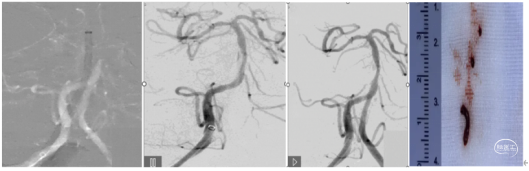

手术过程 造影见右侧颈总动脉造影未见后交通开放,未见基底动脉尖下图1。造影导管超选至右侧椎动脉造影,基底动脉中段闭塞,闭塞远端通过软膜代偿可显影,基底动脉尖显影不佳下图2、3。左侧锁骨下动脉造影见V1段、V2段严重迂曲,遂选择右侧优势椎入路。下图4、5

1、在路图下将260cm长导丝、造影导管超选至右侧椎动脉V2段。撤出造影导管,长导丝交换6F堑远端通路导管及088颅内血栓抽吸导管至V2末端。下图1

2、Transend 200mm 微导丝+Rebar 18 微导管同轴技术将6F远端通路导管及088颅内血栓抽吸导管导引至闭塞段。下图2

3.缓慢上推 088颅内血栓抽吸导管成功上至闭塞段。下图1

4.6F远端通路导管负压抽吸下撤出体外,再次使用088颅内血栓抽吸导管进行充分抽吸,取出部分血栓。下图2

造影显示:未见血管开通。

行球囊穿梭辅助088到达血栓位置:

▪微导丝通过闭塞段,在闭塞远端摆动良好,判断闭塞段相对较短。

▪输送2.0×12mm颅内球囊扩张导管至闭塞段,同时轻柔推送088颅内血栓抽吸导管,顺利通过分叉部,接近闭塞段。088颅内血栓抽吸导管到达目标位置后,充分扩张球囊,缓慢完成球囊穿梭。下图1、2

撤出颅内球囊扩张导管,顺利推送088颅内血栓抽吸导管至基底动脉尖持续抽吸1分钟,保持负压抽吸回撤。下图1

回撤后见血流通畅,基底动脉尖完全再通,无明显血栓逃逸。下图2

观察15分钟以后复查造影,血流维持良好,无明显回缩,(下图3)结束手术。抽吸取出的血栓,下图4